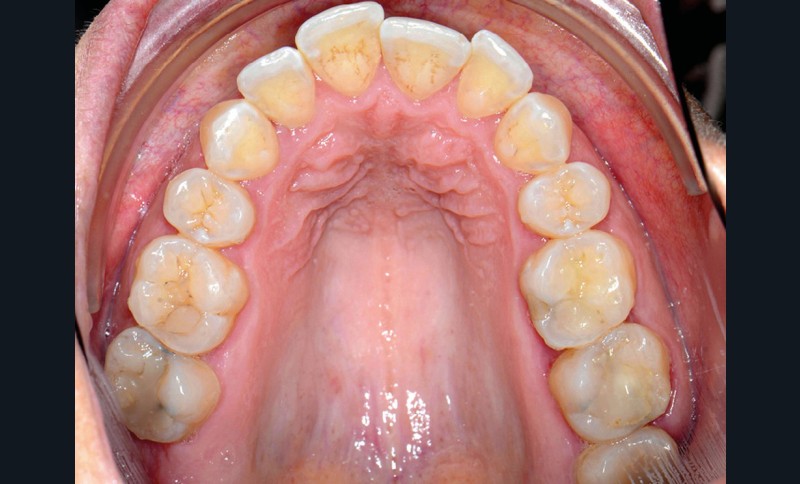

C’est précisément le cas de cette patiente de 33 ans qui présente une classe II squelettique par rétrognathie mandibulaire sur un schéma vertical hyperdivergent associée à une classe II/1 dentaire avec DDA par excès et biproalvéolie. Son profil est convexe, cis-frontal et, sur le plan fonctionnel, on peut observer une dysfonction linguale et une incompétence labiale au repos. Il en résulte une contracture des muscles de la sphère péri-orale lèvres jointes. La formule dentaire n’est pas complète puisque les quatre deuxièmes prémolaires ont été extraites lors d’un premier traitement orthodontique et qu’il y a également agénésie des troisièmes molaires 18 et 38 (fig 1 à 11).

Au regard de ces éléments, la décision thérapeutique choisie intègre une prise en charge orthodontique associée à une chirurgie orthognathique d’avancement mandibulaire et à une mentoplastie. L’étape initiale du traitement orthodontique consiste en la levée des compensations dentaires qui se traduit par la correction de la proalvéolie mandi– bulaire dans le but de pouvoir corriger la classe II squelettique et dentaire par avancement chirur- gical de la mandibule. Pour cela, des mini-vis d’ancrage sont positionnées distalement aux secteurs 3 et 4, enfouies à la base des branches mandibulaires avec des chaînettes métalliques émergentes dans la cavité buccale. L’objectif est d’assurer le repositionnement incisif mandibulaire grâce à des modules élastiques.